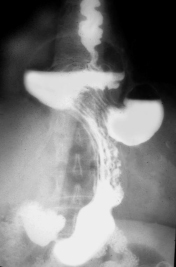

Image TOGD une hernie

hiatale de type III . Estomac en ce cas en roulement

dans le thorax et le cardia glisse au dessus

diapragmatique |